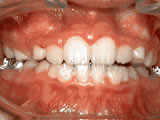

Crowding of the teeth

Patient started treatment at age 11 and wore braces for 26 months. He loves his new smile.